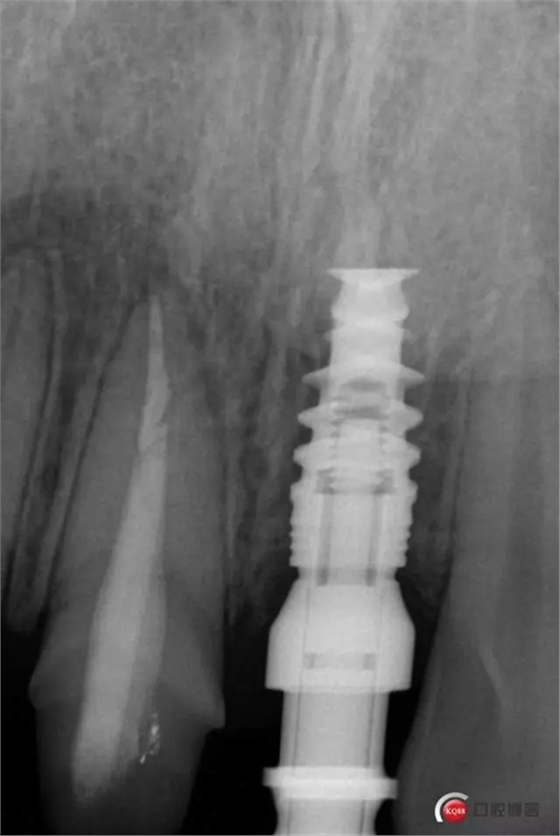

種植后修復(fù),我們要把握每一個(gè)細(xì)節(jié),比色,轉(zhuǎn)移桿的就位,我們必須把臨床做好,技工師傅才會(huì)給我們做出好的修復(fù)體,減少一些不必要的失誤,首先術(shù)前的檢查是必要一步 ,再是器械的準(zhǔn)備使我們臨床操作有條不紊,術(shù)前拍照,o-bite取咬合記錄,消毒修復(fù)術(shù)區(qū),旋出愈合基臺(tái),生理鹽水沖洗袖口,拍照袖口,安放合適轉(zhuǎn)移桿,拍X線見(jiàn)轉(zhuǎn)移桿就為良好,硅橡膠取模,術(shù)后旋回愈合基臺(tái),拍照比色。

藻酸鹽對(duì)頜取模,超硬石膏灌注。發(fā)加工廠,與技工溝通注意事項(xiàng),等修復(fù)體做好后,檢查模型。是否就位,是否密合,預(yù)約患者復(fù)診戴牙,消毒修復(fù)區(qū),旋出愈合基臺(tái),定位器指導(dǎo)安放修復(fù)基臺(tái),試戴冠,調(diào)磨鄰接及 咬合至合適,拋光,患者滿意,加力扳手加力至30N,拍X片見(jiàn)就位良好,特芙蓉及暫封膏封中央螺絲孔,聚羧酸鋅粘固劑粘固,或是樹(shù)脂水門汀粘固,清理多余粘結(jié)劑,光固化樹(shù)脂封螺絲孔,拋光。術(shù)后注意隨訪。